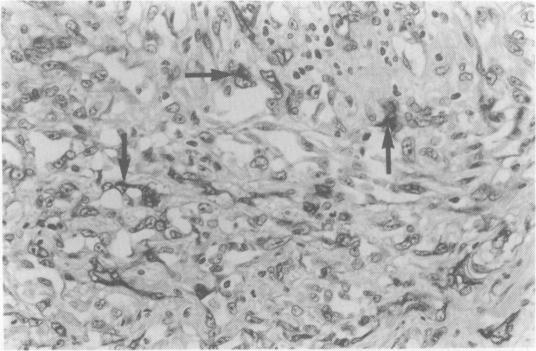

We report a case of angiosarcoma of the glans penis in a 77 year old male Caucasian. The tumour developed 18 years after a course of radiotherapy for a penile ulcer which was an intra-epidermal squamous carcinoma. The differential diagnosis and the concept of radiotherapy-induced angiosarcomas are discussed.